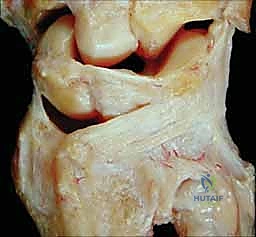

- المفصل الزندي الكعبري البعيد (DRUJ): هو المفصل الذي يربط بين نهايات الكعبرة والزند عند المعصم. يدور عظم الكعبرة حول رأس الزند من خلال هذا المفصل أثناء حركات الكب (تدوير الساعد بحيث يكون باطن اليد لأسفل) والبسط (تدوير الساعد بحيث يكون باطن اليد لأعلى). استقرار هذا المفصل لا يعتمد فقط على العظام، بل يعتمد بشكل كبير على التوافق العظمي بين رأس الزند والثلمة الكعبرية (الشق السيني - Sigmoid Notch) في الكعبرة.

المركب الغضروفي الليفي الثلاثي (TFCC) وأهميته القصوى

يُعد المركب الغضروفي الليفي الثلاثي (Triangular Fibrocartilage Complex - TFCC) بمثابة "غضروف الركبة" بالنسبة للمعصم. إنه هيكل معقد يتكون من أربطة وغضاريف تربط المفصل الزندي الكعبري البعيد بعظام الرسغ.

* وظيفة الـ TFCC: يوفر استقرارًا حيويًا للمفصل (DRUJ)، ويساعد في امتصاص الصدمات وتوزيع الأحمال الميكانيكية عبر المعصم أثناء رفع الأشياء الثقيلة أو الاستناد على اليد.

* الارتباط بالناتئ الإبري: ترتبط العديد من أربطة الـ TFCC مباشرة بالناتئ الإبري للزند (Ulnar Styloid). لذلك، فإن أي كسر في قاعدة الناتئ الإبري غالبًا ما يصاحبه تمزق في هذا المركب الغضروفي، مما يؤدي إلى عدم استقرار شديد في المعصم يستوجب تدخلًا جراحيًا دقيقًا، وهو ما يبرع فيه الأستاذ الدكتور محمد هطيف باستخدام تقنيات المناظير (Arthroscopy).

الأربطة الزندية الكعبرية (Radioulnar Ligaments)

تُعتبر الأربطة الزندية الكعبرية (الظهرية والراحية) حاسمة لاستقرار المفصل. تنشأ هذه الأربطة من نقرة رأس الزند (Fovea) وقاعدة الناتئ الإبري، وتتصل بالحواف الظهرية والراحية للثلمة الكعبرية.